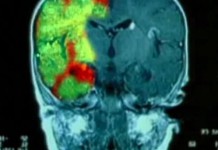

Функциональная томография

В Федеральном научном центре неврологии установлен уникальный прибор, который позволяет не только определить зону поражения мозга при инсульте, но и оценить, насколько серьезно пострадали нервные клетки.

Магнитно-резонансный томограф

При самых первых признаках инсульта необходимо срочно сделать магнитно-резонансную томографию. Эта процедура позволит не только избежать тяжелых последствий инсульта, но и спасти жизнь.